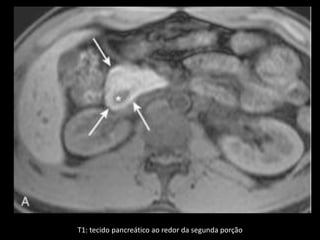

Pâncreas anular

A CPER mostra um ducto pancreático aberrante

circundando o duodeno.

O local de drenagem desse ducto é variável;

A RM e a TCMD mostram tecido pancreático

circundando o duodeno, que conserva a densidade

e a intensidade de sinal do pâncreas normal

remanescente, tanto no exame basal como após a

administração de contraste.

Imagens T1 com supressão de gordura são úteis.

Diferenciação com neo pancreática ou duodenal.

T1: tecido pancreático ao redor da segunda porção